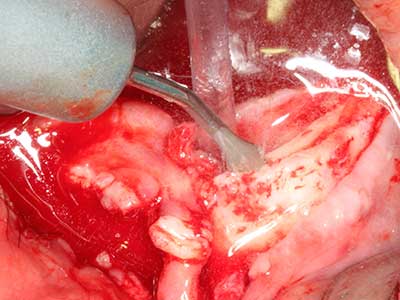

Sollen chirurgische Eingriffe mit unmittelbarer Knochenbeziehung an empfindlichen Strukturen wie Blutgefäßen oder Nerven erfolgen, so bergen rotierende Instrumente ein erhebliches Potential an iatrogener Schädigung. Gerade bei Nervdarstellungen nach iatrogener Schädigung, oder aber im Zuge einer Nervlateralisation für resektive und rekonstruktive Eingriffe oder Implantatinsertionen können piezoelektronische Geräte hilfreich sein Knochendeckel zu präparieren und nervnahe Hartgewebsanteile zu entfernen (Abb. 17-20). Ein leichter Kontakt des Nervstrangs zur Piezospitze bleibt dabei in der Regel folgenlos – allerdings kann eine unvorsichtige Vorgehensweise mit sägeartigen Bewegungen bzw. Ansätzen bei noch vorhandener knöcherner Unterlage durchaus temporäre oder aber auch permanente Nervschädigungen verursachen. Das Risiko einer solchen Schädigung wird jedoch als wesentliche geringer eingeschätzt als unter Anwendung von Säge- oder Fräsinstrumenten (Pereira, Gealh et al. 2014).

Indikation: Wurzelspitzenresektion